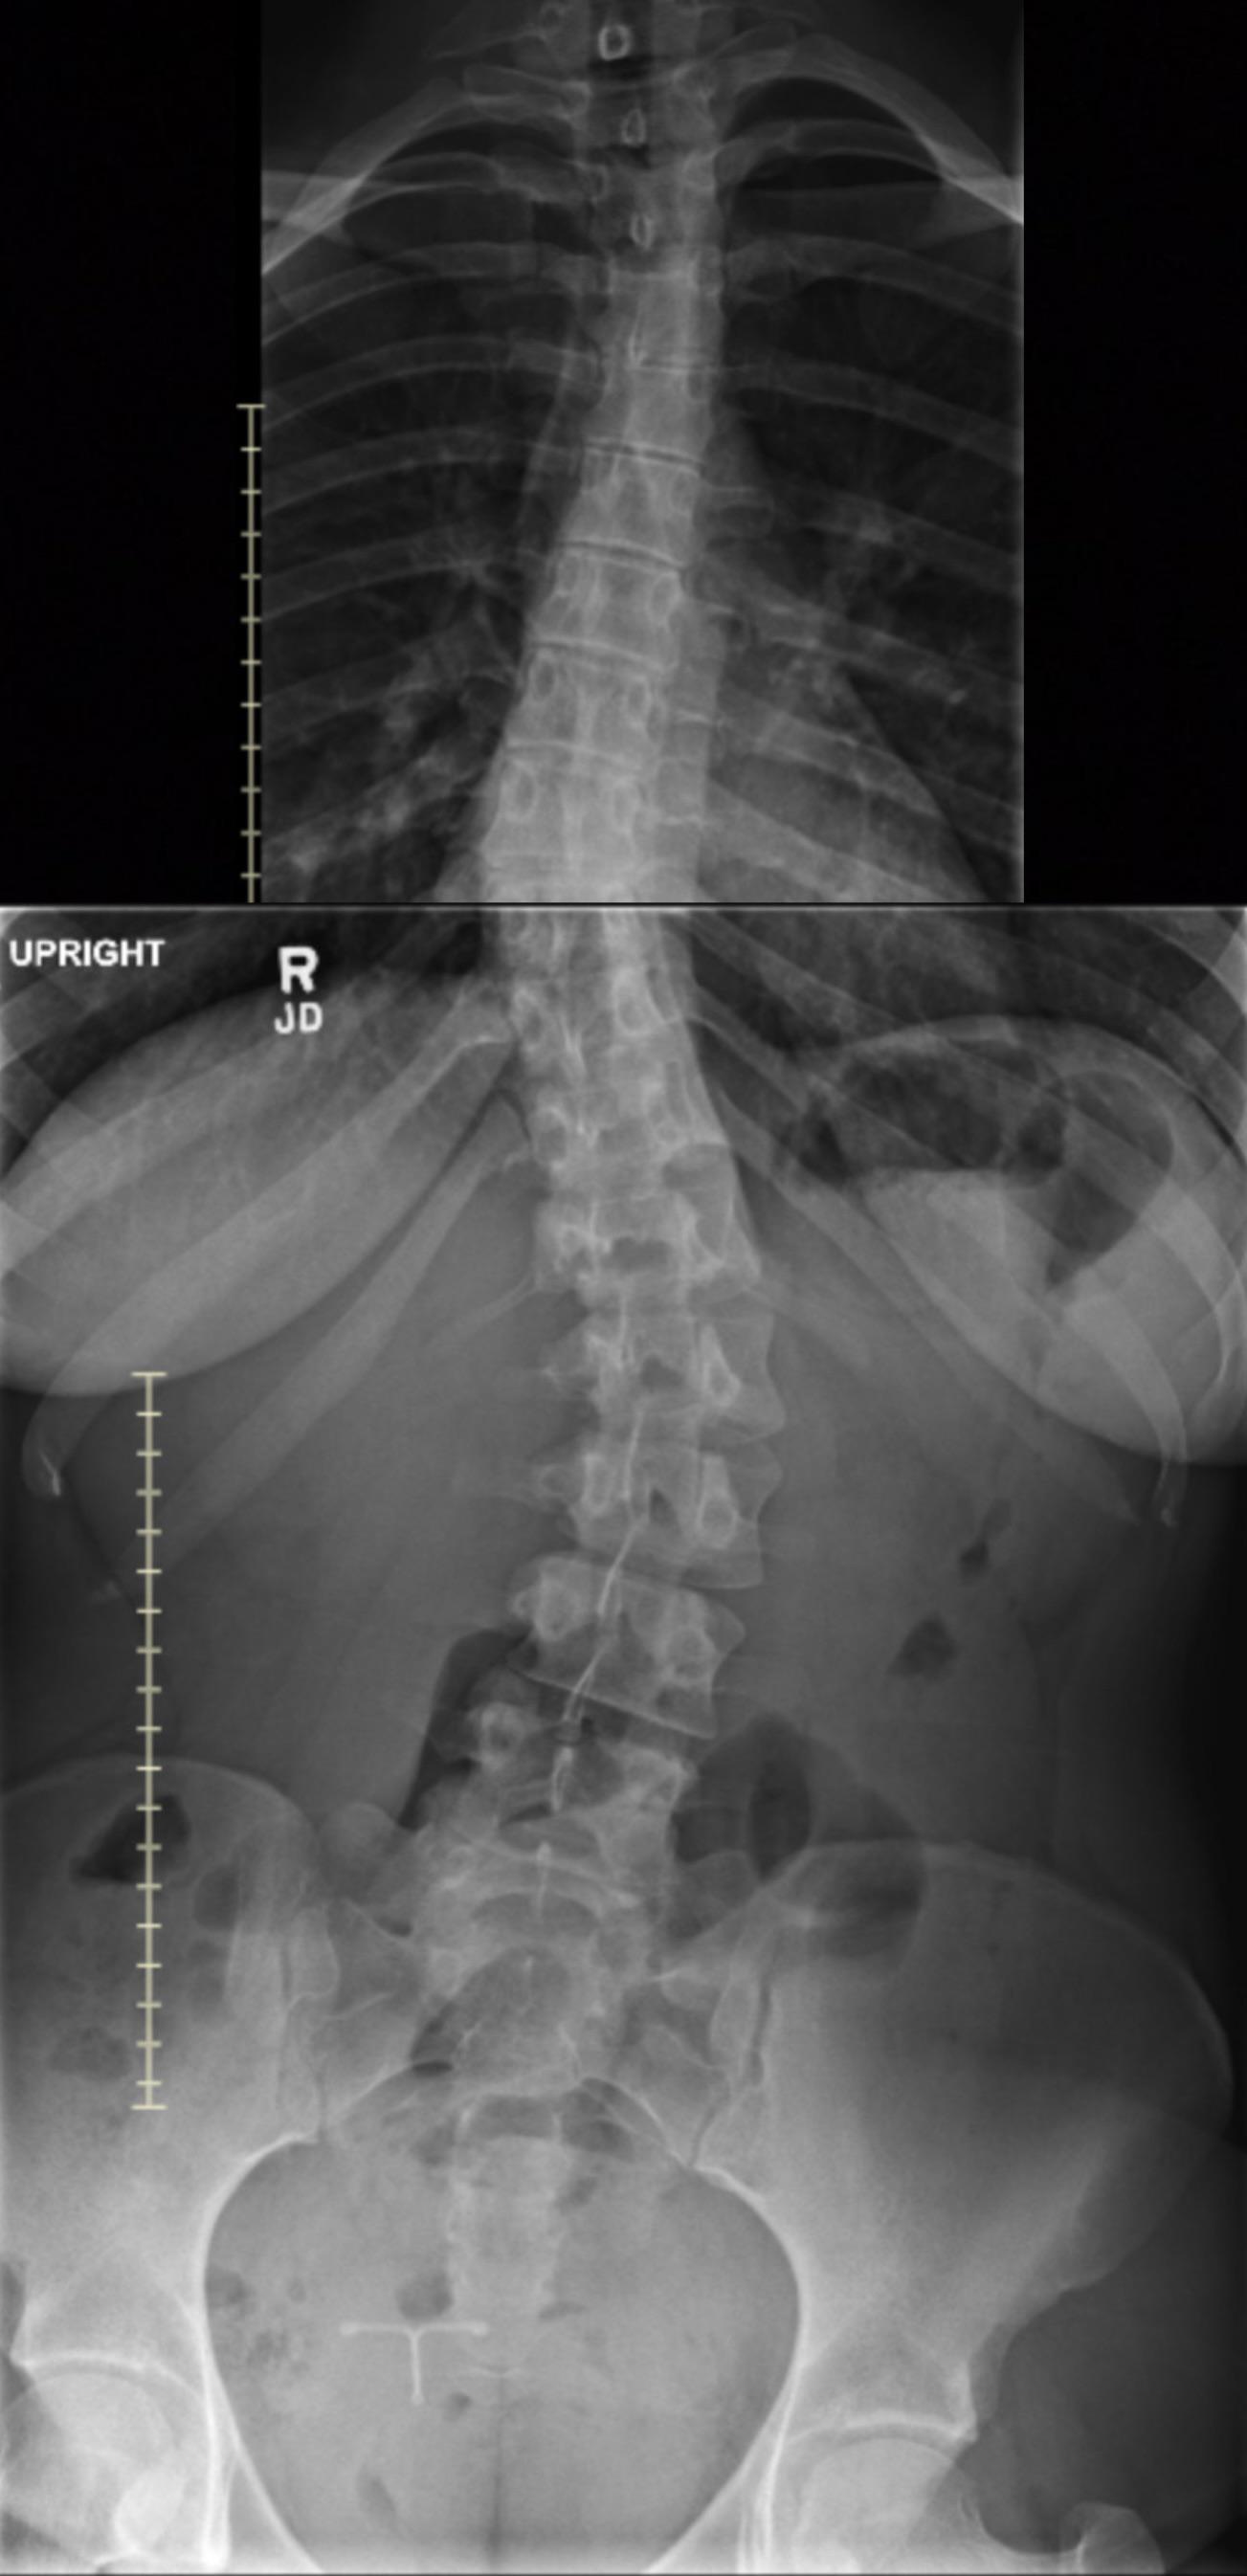

They’re translucent irl too